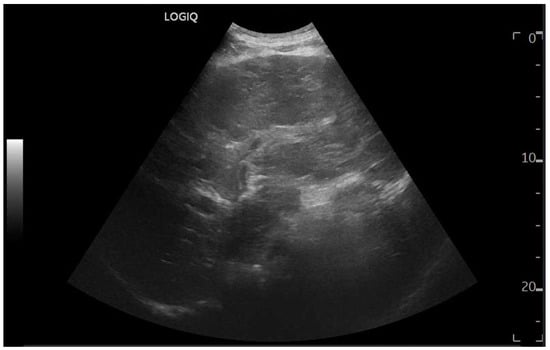

Ultrasound imaging is capable of identifying heterogeneous echotexture and hepatomegaly, which are early indicators of congestive hepatopathy [46]. Several studies have shown correlations between the extent of sonographic abnormalities and the severity of hepatic fibrosis or cirrhosis [36,47,48]. The most common ultrasound findings encompass a nodular hepatic surface, right-lobe volume reduction, smooth-to-rounded contour changes, and irregular outer profiles [49,50,51] (Figure 2). The echotexture appears granular and markedly heterogeneous, with hyperechogenic nodules of varying sizes [49,50,51] (Figure 3, Figure 4, Figure 5, Figure 6, Figure 7 and Figure 8).

Figure 4.

Oblique subcostal scan with convex probe showing diffuse periportal edema.